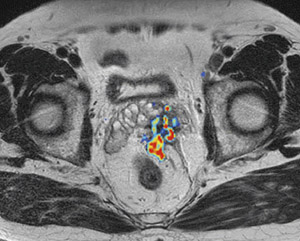

腹部のMRI MRI of the thoracic and the lumbar spine. A: sagittal T2の詳細情報

MRI of the thoracic and the lumbar spine. A: sagittal T2。116D52 | 卵巣腫瘍 国試 | テコプラ。腹部領域のMRI最新アプリケーション-技術解説 - 株式会社日立。Vertebral Compression Fracture - MRI Images - The Pain。「腹部のMRI」荒木 力定価: ¥ 13000#荒木力 #荒木_力 #本